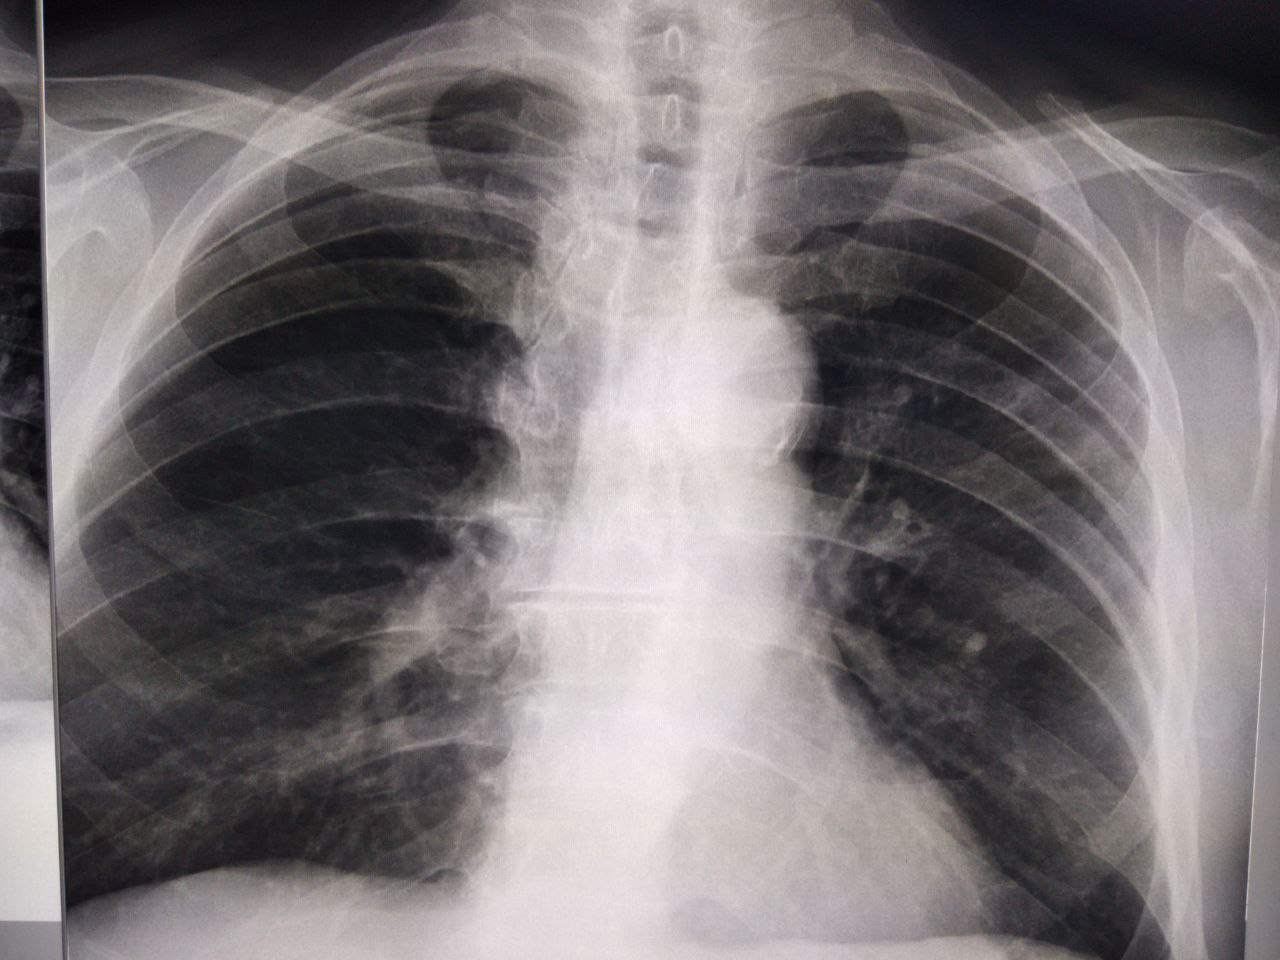

Нурбану Сериковна... in Radiology/Рентгенология Чатоид

источник

Как можно описать снимок